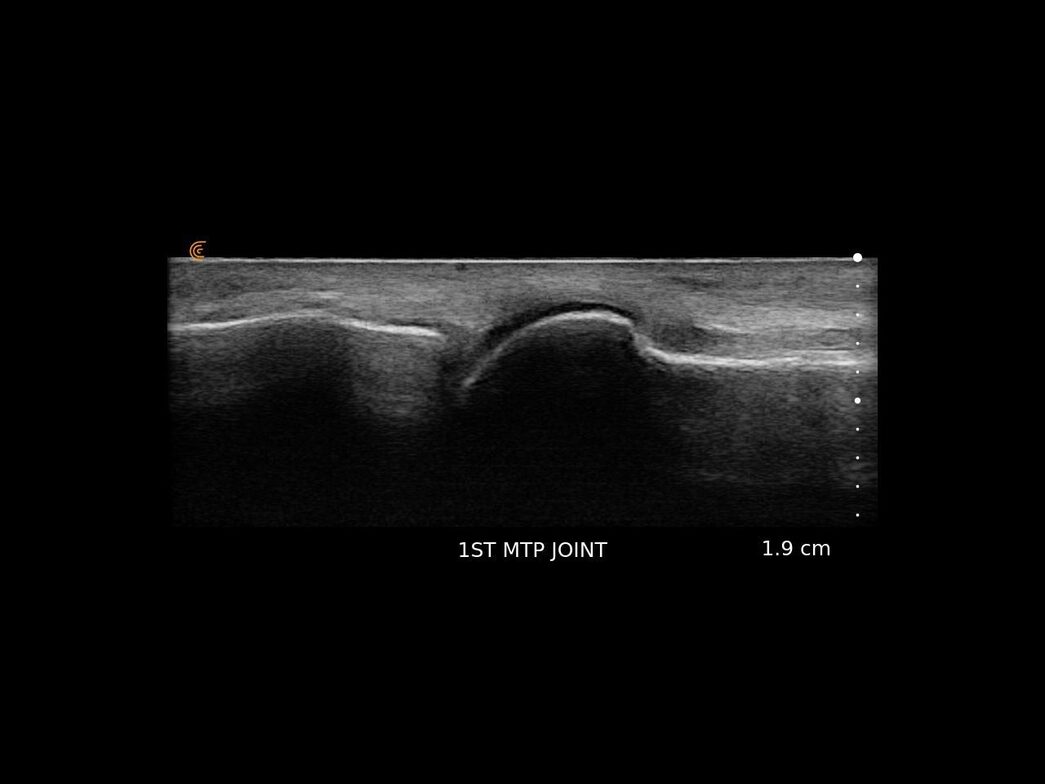

This last six months we have been able to offer patients the incredible ability to see their own foot/leg condition on a big high resolution screen.